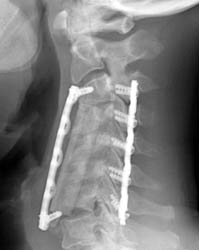

63 yr old with progressive myelopathy and severe cervical spondylosis. Patient underwent 3 level corpectomy (C4-6) and anterior cervical fusion to decompress the spinal cord ventrally and return some cervical lordosis.

Lateral radiograph taken immediately after the initial operation. The C4, C5, C6 corpectomies with central strut graft placement is seen, and an anterior fixation plate with screws at the C3 and T1 levels are identified. No immediate hardware complications noted.

Lateral radiograph 4 months post-op demonstrating the strut graft now  displaced anteriorly, and the inferior fixation screw is not located in the vertebral body. No acute fracture seen.